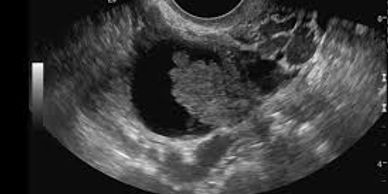

Ovarian cancer is a cancer that forms in an ovary.In 2012, ovarian cancer occurred in 239,000 women and resulted in 152,000 deaths worldwide. This makes it, among women, the seventh-most common cancer and the eighth-most common cause of death from cancer. Death from ovarian cancer is more common in North America and Europe than in Africa and Asia.